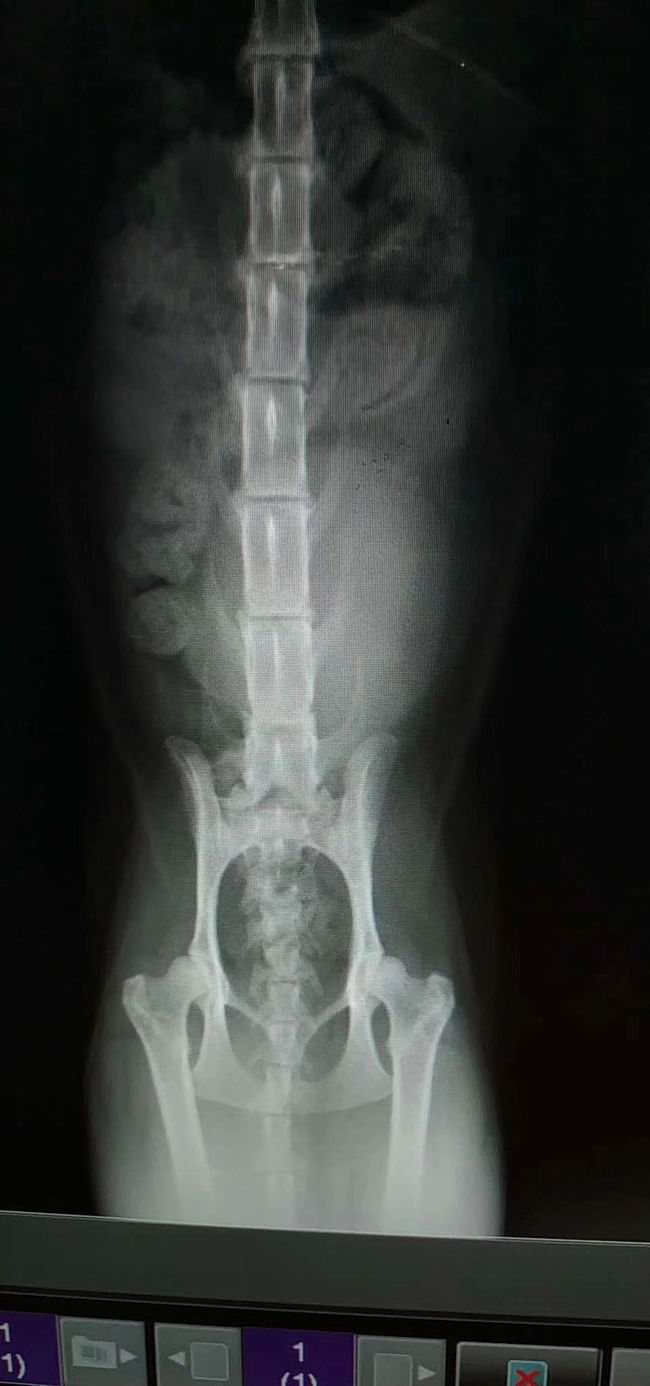

本月又一急診尿閉病例恢復(fù)/出院穩(wěn)定:黑子,母喵,尿閉,經(jīng)住院治療,體征已穩(wěn)定,主人帶回護(hù)理。